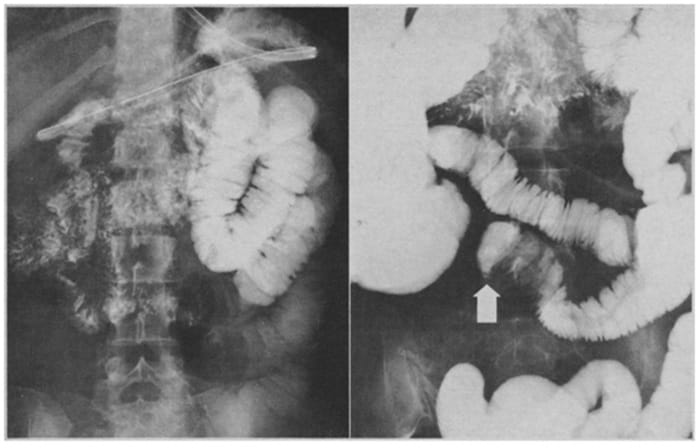

2.2. Chụp X-quang đại tràng có cản quang (Barium enema)

Chụp X-quang đại tràng có cản quang hay còn gọi là thụt bari, là phương pháp chẩn đoán hình ảnh dùng để quan sát cấu trúc bên trong đại tràng. Trong quá trình thực hiện, bác sĩ sẽ bơm dung dịch Barium sulfate (chất cản quang) vào đại tràng qua đường hậu môn. Chất này giúp phủ đều niêm mạc ruột, làm nổi bật hình ảnh khi chụp X-quang, từ đó phát hiện các bất thường như hẹp, viêm, loét, khối u hoặc polyp lớn.

Ưu điểm:

- Thủ thuật đơn giản, chi phí thấp, phổ biến.

- Không cần gây mê, không xâm lấn, người bệnh ít khó chịu hơn so với nội soi.

Nhược điểm:

- Độ phân giải thấp, khó phát hiện các tổn thương nhỏ hoặc phẳng.

- Không thể sinh thiết hoặc cắt polyp nếu phát hiện bất thường.

- Độ chính xác trung bình 70–80%, chỉ phù hợp khi không thể thực hiện nội soi trực tiếp.

Chụp X-quang nhanh chóng với chi phí thấp